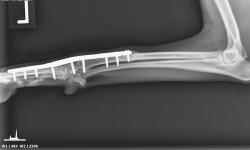

Pacient č. 3. - předoperační rtg.

Pacient č. 3. - použití implantátu Fixin Intrama.

Pacient č. 3. - pooperační rtg.

Pacient č. 3. - po operační rtg 2.